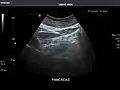

Pancreas: Visualized portions unremarkable.